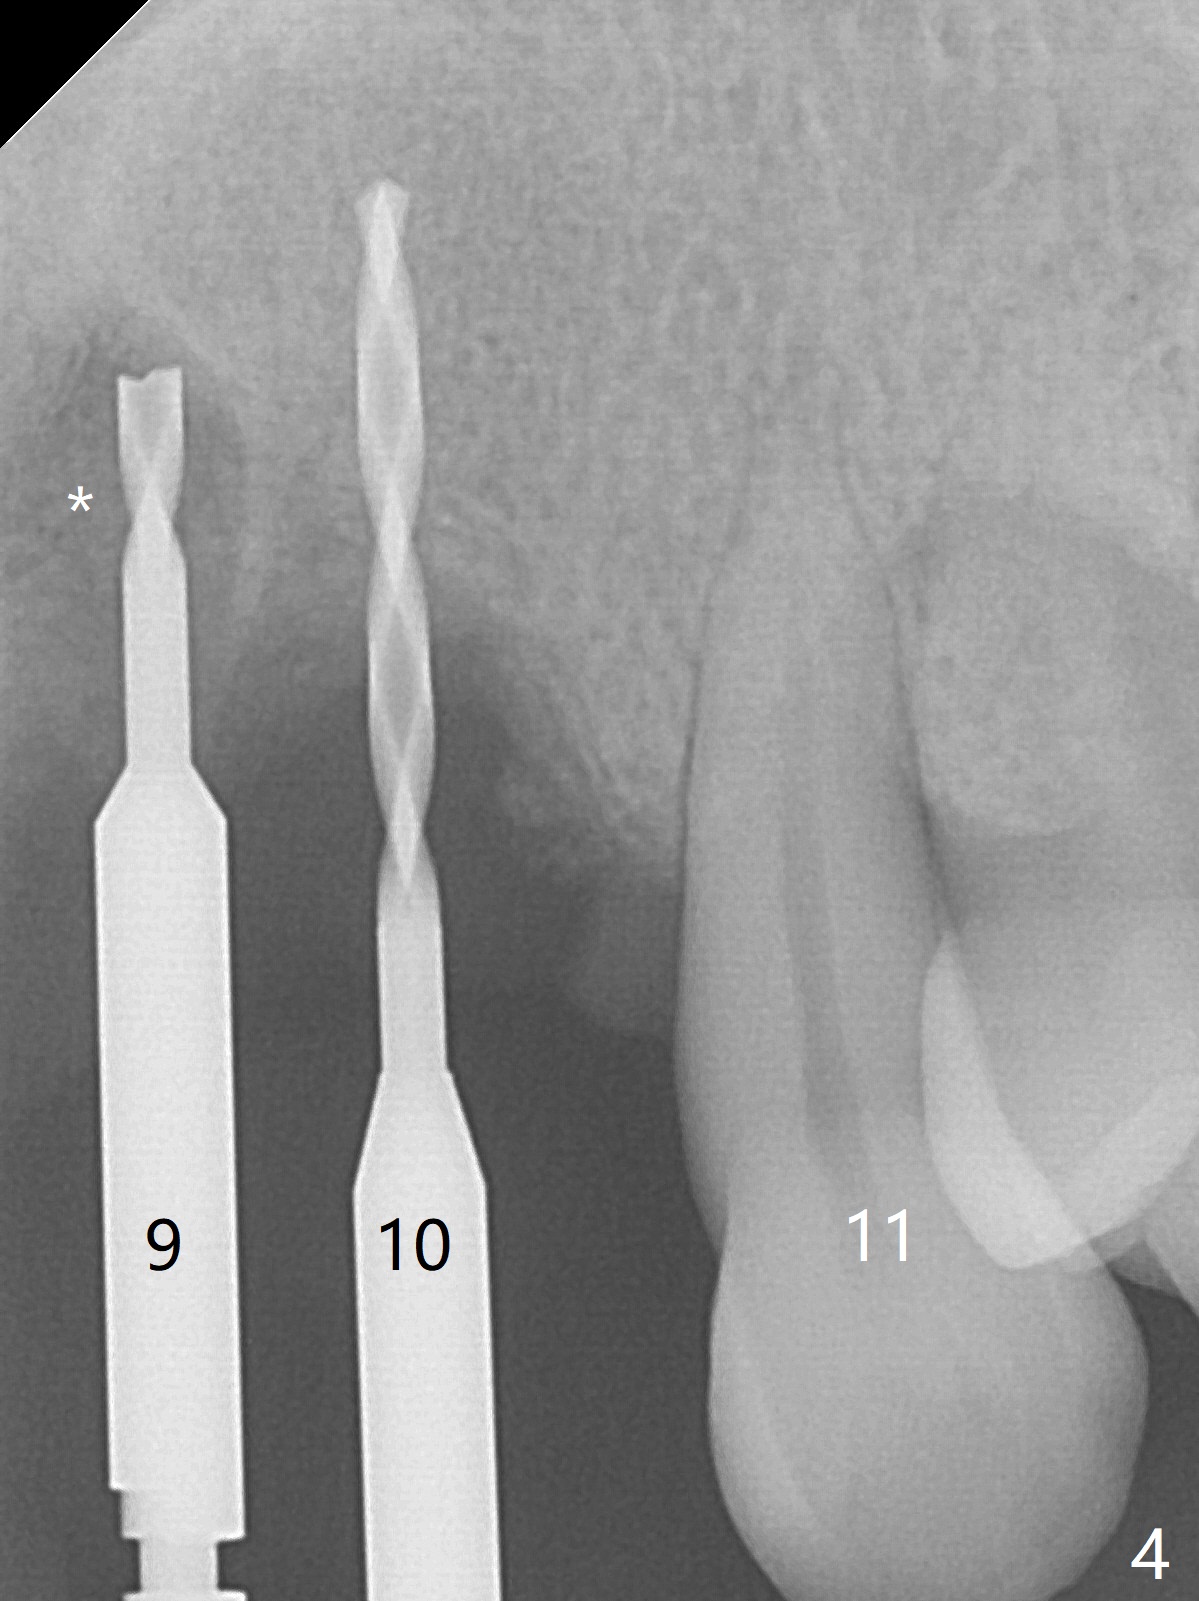

Although the ridge of the maxillary anterior ridge looks moderate in width (Fig.1), the bone is ~4 mm buccopalatally. Suction down surgical stent (Fig.2') made from the lab-fabricated provisional (Fig.2) will be used to check the position and trajectory of osteotomies. PAs taken after initial osteotomies (1.2 mm drill) show those at the central incisors tend to be mesial (close to the Incisive Canal *), while those at the lateral incisor sites distal (Fig.3,4). After adjustment, the position and trajectory of the osteotomies are acceptable (Fig.5,6). To reduce the chance of perforating the Incisive Canal (Fig.3,4 *), 2.5 mm 1-piece implants are inserted with >40 Ncm (Fig.7,8). After deep placement of the implants, Vanilla graft is placed at the crest (Fig.9,10 *). An immediate splinted provisional is fabricated from the suction down stent. The gingiva is healthy around the provisional (Fig.11) and the implants (Fig.12,13) 1 month postop. The provisional is adjusted monthly so that the interdental papillae can be elongated. No bone resorption is observed 6 months postop (Fig.14,15). Crowns are cemented 8 months postop (Fig.16-18). The keratinized gingiva appears to have formed the abutments 8 months postop immediately pre-cementation (Fig.19).